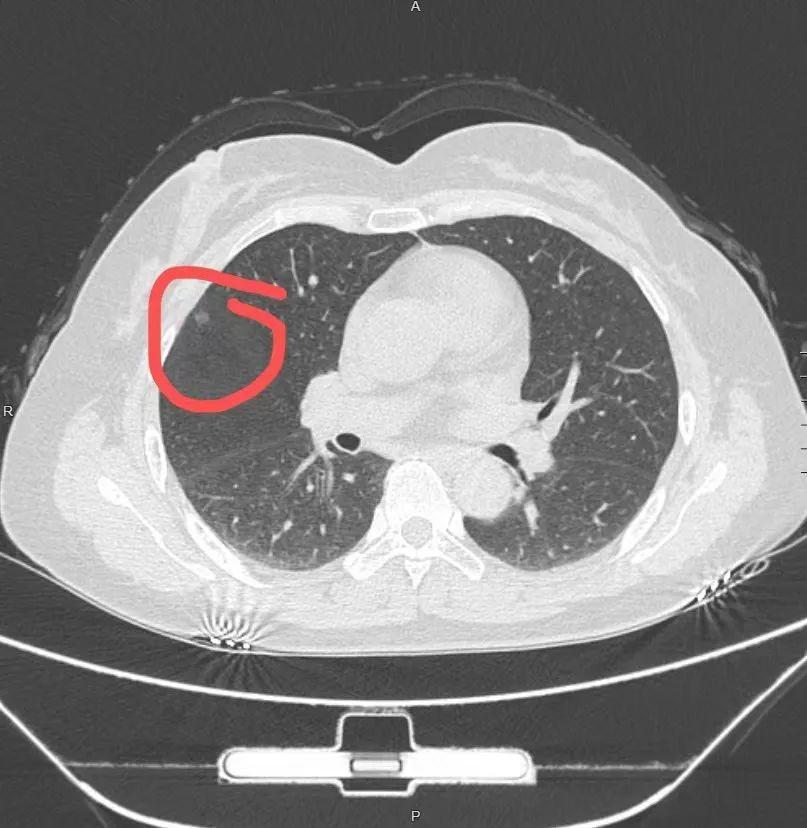

45岁的张明在一次例行体检中被发现右肺有一个0.8厘米的结节。医生告诉他, 大多数肺结节是良性的 ,但需要进一步检查以确定性质。张明的第一反应是:“我需要立即手术吗?”医生解释说,手术并不是第一选择,而是需要根据一系列检查结果来决定。

首先,医生会评估肺结节的大小、形状和增长速度。根据2023年发布的《肺部结节(≤2 cm)楔形切除胸外科全国专家共识》,直径小于1厘米的结节通常建议随访观察。因此, 张明的结节暂时不需要手术

接下来,医生可能会建议进行低剂量CT扫描。这种检查可以更清晰地显示结节的特征,如边缘是否光滑、内部是否有钙化等。 如果CT显示结节有恶性特征,如边缘不规则或有毛刺,那么手术的可能性就会增加